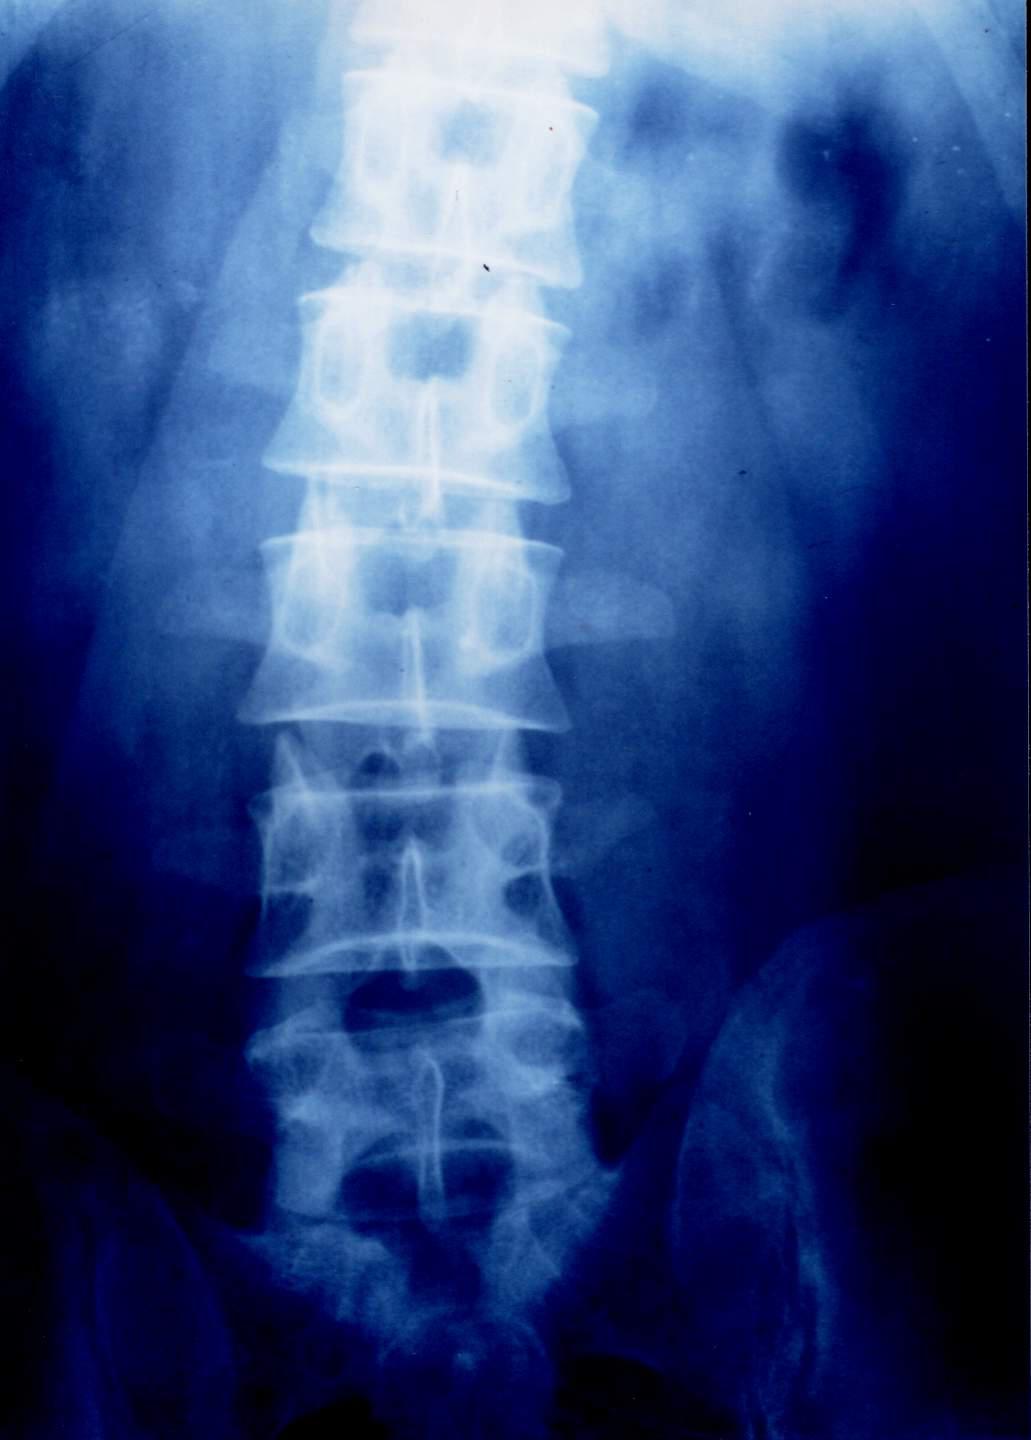

先来看看正常人体的脊柱整体情况,如下图:

腰椎间盘突出针灸有副作用吗,腰椎间盘突出针灸越来越严重

请把头偏向右侧,侧着看我们的脊柱,是不是很像一条蜈蚣,千足之虫。而这蜈蚣一节一节的就叫做脊柱的椎体,根据部位的不同,分别称为颈椎、胸椎、腰椎以及屁股部位的骶骨、尾骨。

X线平片:对于骨科医生来说,一张简单便宜的X线片,往往比任何检查都重要,可以根据脊柱的弯曲度、椎间隙的变化,来间接推断出是否存在椎间盘突出,缺点是老百姓可能看得一头雾水,不知所以然!